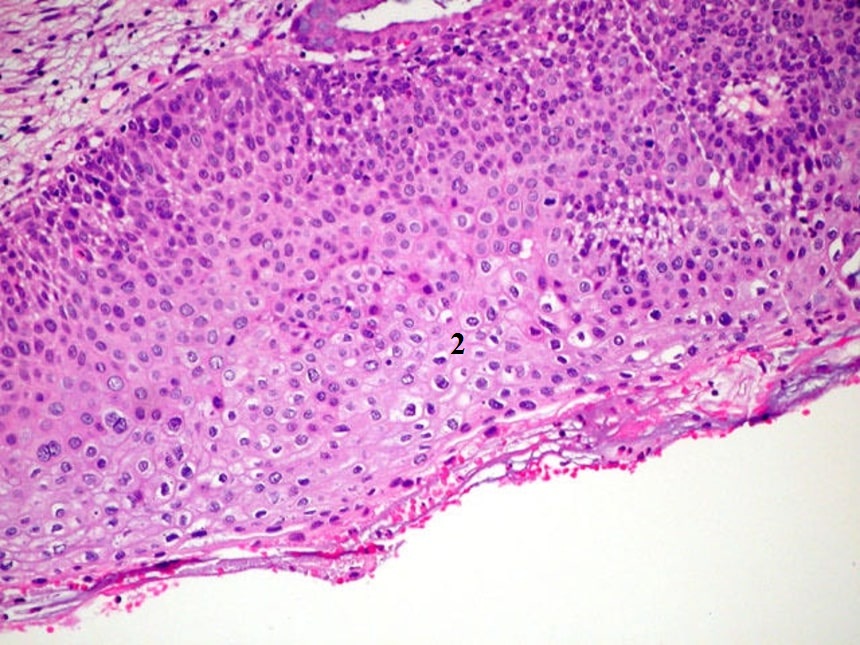

Наботовы кисты – это доброкачественные образования, которые формируются при перекрытии протоков желез на ее поверхности с последующим скоплением слизистого секрета в закупоренном пространстве. Такое состояние способно развиваться у женщин любого возраста; тем не менее, чаще всего оно встречается среди молодых пациенток, активно ведущих сексуальную жизнь. В репродуктивные годы данная патология обычно связана с вагинальными или цервикальными воспалительными процентами – вагинитом и цервицитом. С началом климакса риск появления кист увеличивается из-за атрофии тканей, вызванной снижением концентрации эстрогенов.

Рисунок 3 - Наботова киста шейки матки указана на рисунке цифрой 1

Примечание: окрашивание гематоксилином и эозином; увеличение х25

Наботовы кисты встречаются в 40% случаев у женщин детородного возраста, у женщин среднего возраста риск развития кист снижается.